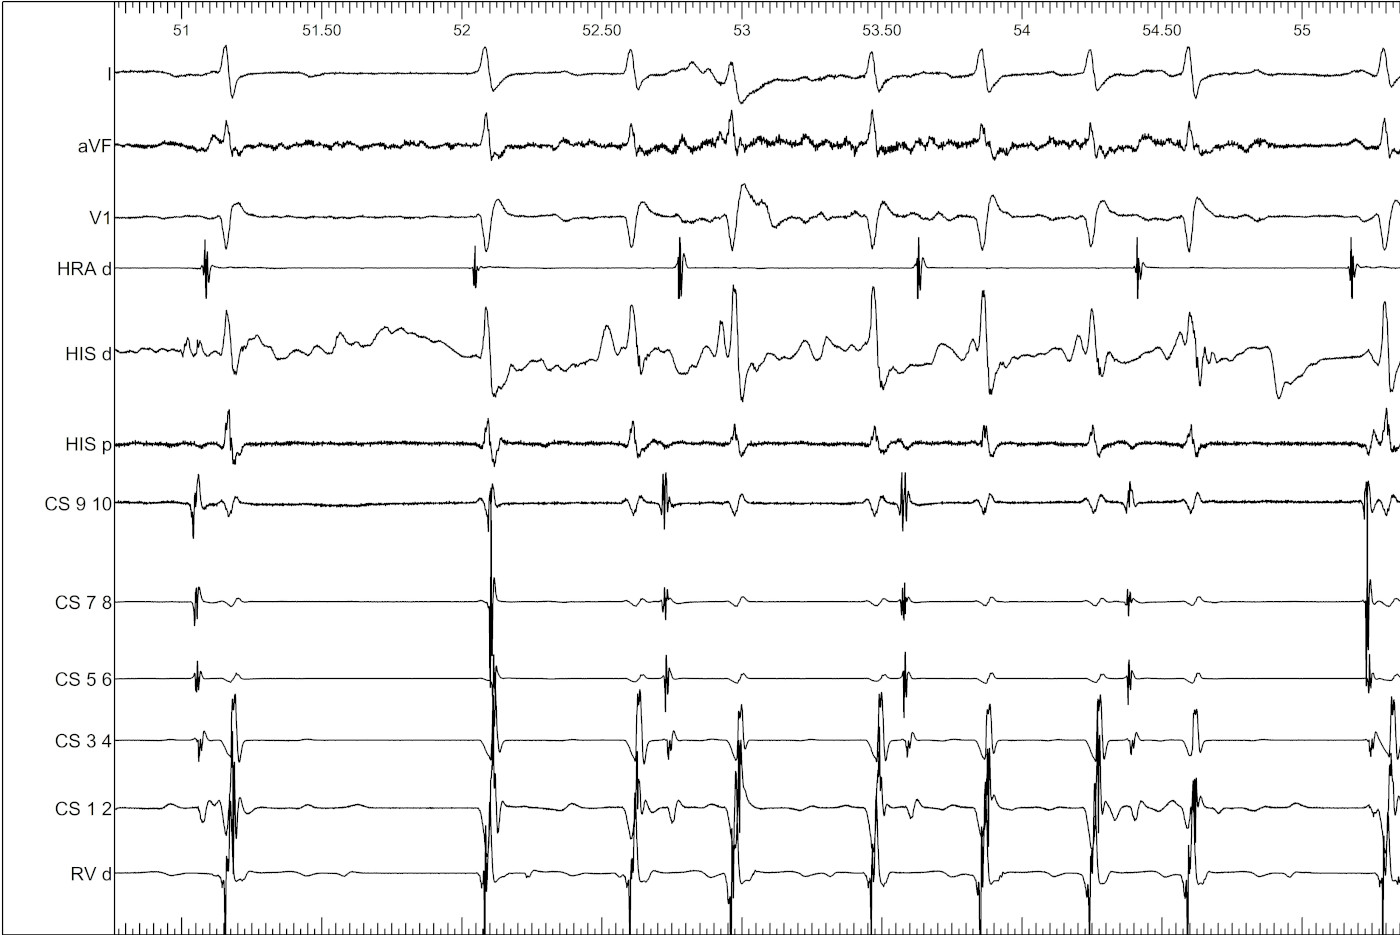

Young male, RHD MS with left sided AP, preexcited AF

palani_002.jpg

Mapping during AF

palani_006.jpg

Ablation during AF

palani_004.jpg